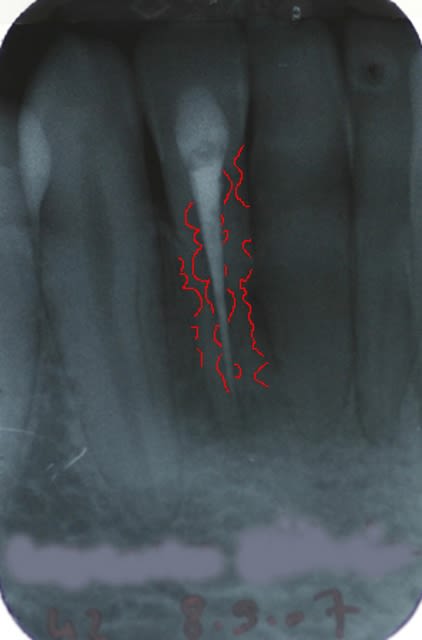

J'ai retraité la 42 en octobre 2007. Cette dent avait subi un traumatisme il y a une dizaine d'année. A la radio de contrôle d'hier, il semble qu'une resorption se soit développée en mésial, au niveau cervical en regard de la chambre.

Faut-il faire un lambeau d'accès et obturer cette résorption? avec du MTA?

Euh cher Saint Desmotome, t'appelle ca 1 résorption ??!!

Ok Olivier. Si j'ai bien compris pour toi c'est extraction sans attendre.

De mon côté c'est vrai que j'étais tenté d'être conservateur vu que la dent est totalement asymptomatique et que l'environnement est particulièrement sain.

La dent présentait déja des resorptions bien visibles sur la radio préoperatoire, ce qui est tres fréquent sur les dents traumatisées.

Le plus judicieux a l'epoque du traitement aurait été de passer par des étapes d'hydroxde de calcium renouvlé jusqu'a stabilisation des résorptions.

Je suis tout à fait d'accord avec Stephane dans le sens où la dent ne présente pas de problème paro associé. Dans le cas que tu nous montres et à la vue de ta rétro, je suis sceptique sur le fait que tu n'aies pas de perte d'attache en mésial.

L'os interdentaire au niveau du bloc incisif mandibulaire est très fin, et si tu perds cet os, ton traitement implantaire, si c'est ce qu'il est prévu de faire pour remplacer la dent dans le futur, peut être particulièrement compliqué (perte osseuse mesiale, perte papillaire).

Si la dent à un pronostic qui dans tous les cas est mauvais , si le patient veut remplacer la dent par un implant, je reste sur mes dires et préfère et recommande d'extraire la dent tant que tu as de l'os approximal.

Si prothèse conventionnelle prévue alors oui tu peux conserver la dent tant que la patient n'a pas de symptome.

Je confirme qu'il n'y a ni perte d'attache mésiale, ni aucun symptome. La patiente est jeune, 21 ans, a une très jolie bouche et une hygiène irréprochable. Aucun soin dentaire si ce n'est 42 et 21, dévitalisées toute deux suite au même traumatisme. Dans ce contexte, c'est naturellement la solution implantaire qui sera choisie le jour où il faudra remplacer cette dent. Avec un environnement favorable comme celui-ci, penses-tu que le fait de temporiser puisse mettre en péril le succès esthétique du futur implant?